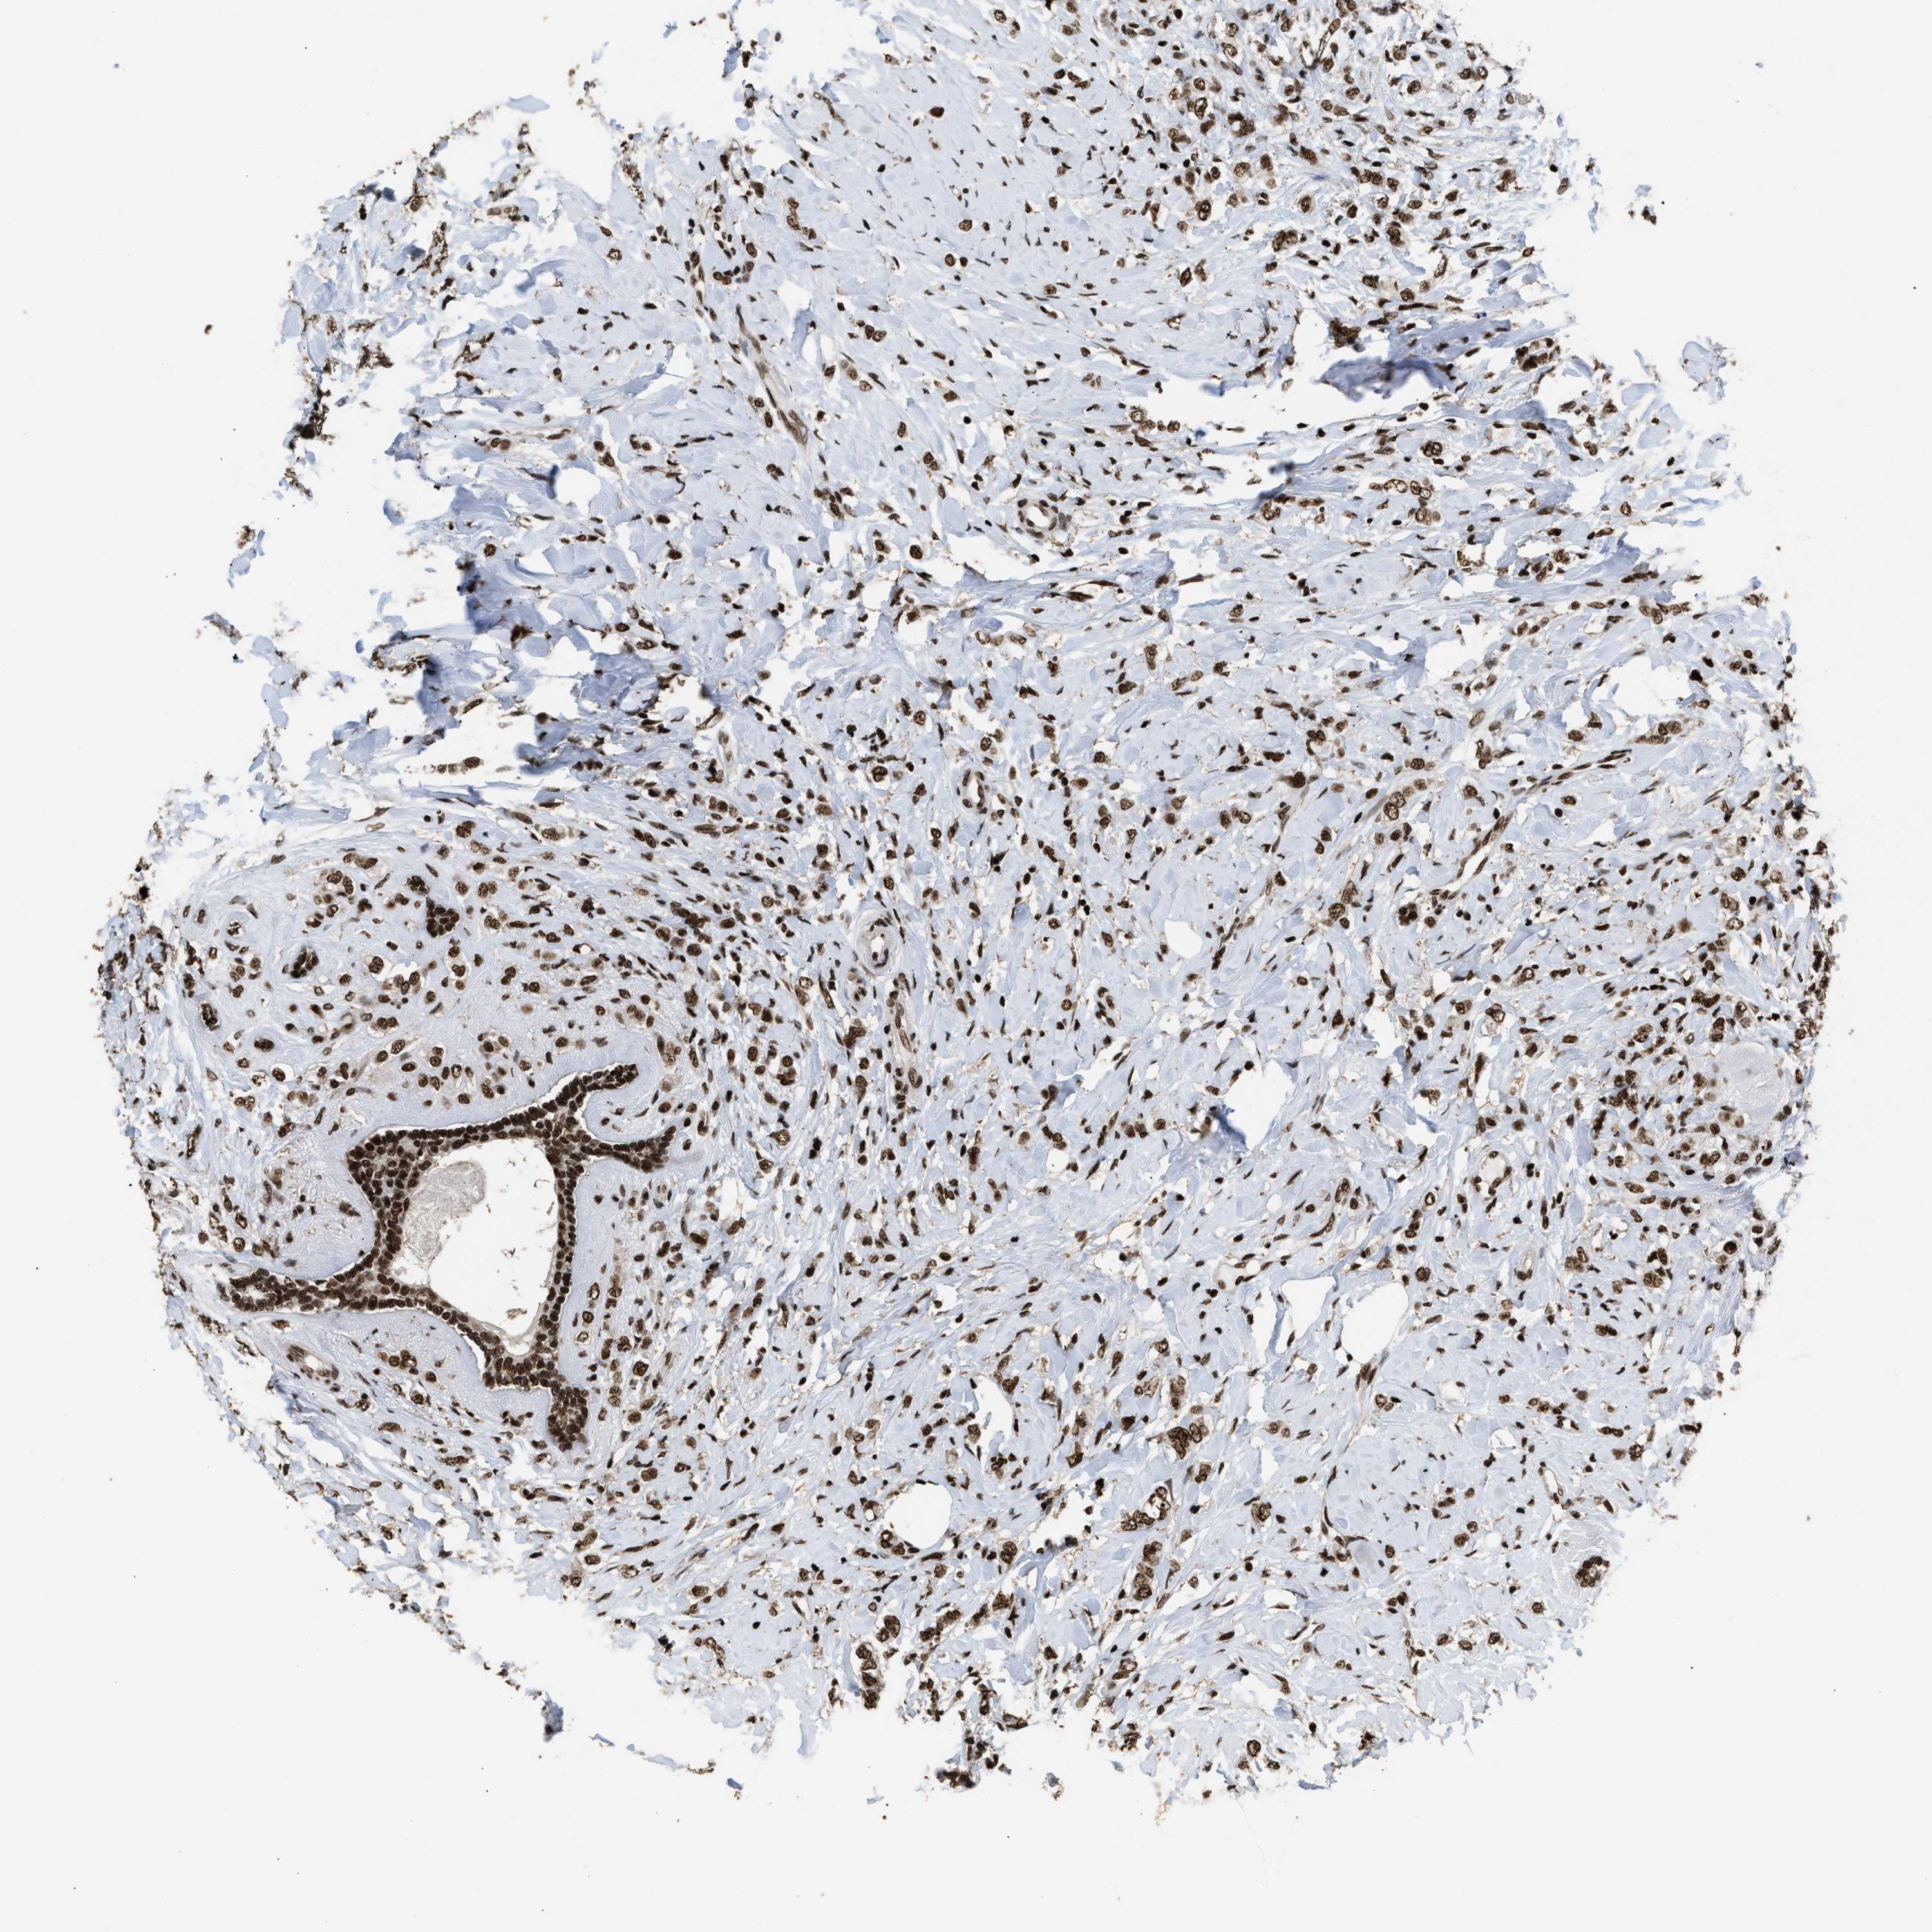

CANCER BREAST CANCER Show tissue menu

BRCA TCGA BRCA VALIDATION PROTEIN EXPRESSION